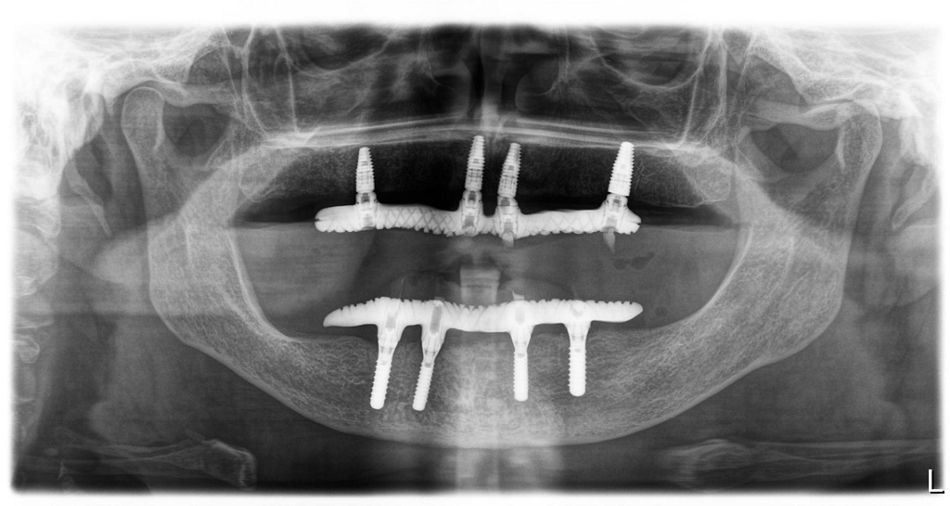

Иллюстрация 10

В течение 3 рабочих дней проведена фиксация временных условно съемных протезов на винтовой фиксации на верхней и нижней челюсти. Шахты закрыты тефлоновой лентой и композитным материалом Gradia A2 (Илл. 11-13).

На нижней челюсти установлены 4 дентальных имплантата Straumann SLActive®:

3.2 – Straumann SLActive® SP 3.3х14 мм. Получена первичная стабильность имплантата 45 Н/см. Установлен формирователь десны высотой 4 мм.

3.4 – Straumann SLActive® SP 4.1х14 мм. Получена первичная стабильность имплантата 40 Н/см. Установлен формирователь десны высотой 4 мм.

4.2 – Straumann SLActive® SP 3.3х14 мм. Получена первичная стабильность имплантата 35 Н/см. Установлен формирователь десны высотой 4 мм.

4.4 – Straumann SLActive® SP 4.1х14 мм. Получена первичная стабильность имплантата 45 Н/см. Установлен формирователь десны высотой 4 мм.

Установлено 4 имплантата Straumann SLActive® с параметрами:

1.1 – Straumann SLActive® BLT 4.1х12 мм. Получена первичная стабильность имплантата 35 Н/см. Установлен формирователь десны.

2.1 – Straumann SLActive® BLT 4.1х12 мм. Получена первичная стабильность имплантата 40 Н/см. Установлен формирователь десны.

1.6 – Straumann SLActive® BLT 4.1х10 мм. Получена первичная стабильность имплантата 40 Н/см. Установлен винт-заглушка.

2.6 – Straumann SLActive® BLT 4.8х12 мм. Получена первичная стабильность имплантата 45 Н/см. Установлен винт-заглушка.